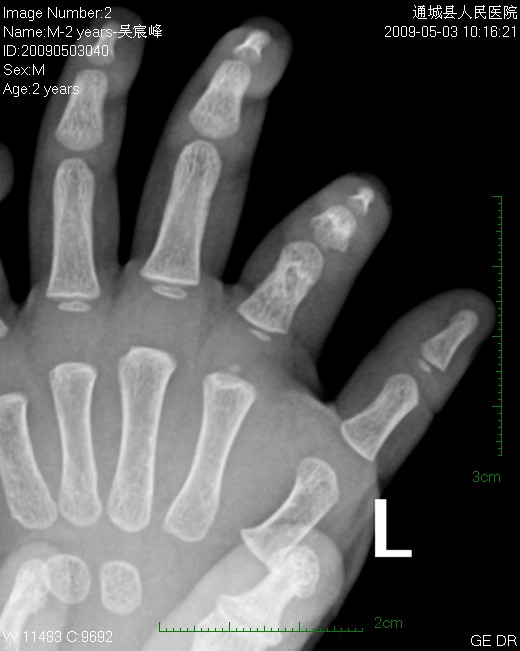

男  2岁  左手食指发育短小,指骨粗短,外表肤色、功能无异。

指骨发育缓慢,考虑内生软骨瘤。

软骨发育不良所致

指骨发育不全,楼主所指有可能